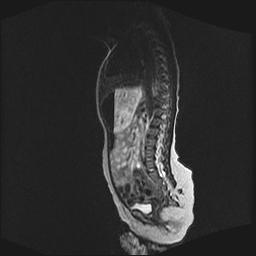

标题: PED0016:脊膜膨出 [打印本页]

标题: PED0016:脊膜膨出

四个月的女婴,ct示脊膜膨出.

脊柱裂、脊膜膨出,请结合临床除外皮毛窦。

脂肪脊髓脊膜膨出

脊柱裂、脊膜膨出